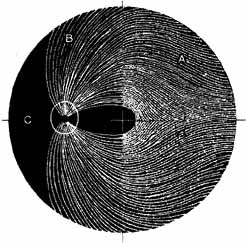

Visual field testing can also be helpful in diagnosis of orbital processes. Optic disc–associated visual field changes are usually altitudinal because of the structure of the horizontal raphé (Fig. 13). This visual field defect is typically a result of anterior ischemic optic neuropathy (AION).24 Compressive lesions of the orbit or retrobulbar inflammation are more likely to produce a central or cecocentral scotoma. However, one must be aware that there is a significant degree of overlap between various types of optic nerve lesions and visual field abnormalities.25 In these cases, neuroimaging may be a useful adjunct in differentiating between different neuro-ophthalmic and orbital processes.26

Fig. 13 Pathway of ganglion cell axons that originate temporal to the macula (A) do not cross the horizontal meridian. Any damage to the superior ganglion cell axons at the optic disc will generate atrophy within the superior nerve fiber layer (B). The visual field defect will be inferior but not crossing the horizontal plane. (Hoyt WF, Rios-Montenegro EN, Behrens MM, et al: Homonymous hemioptic hypoplasia: funduscopic features in standard and red-free illumination in three patients with congenital hemiplegia. Br J Ophthamol 56:537, 1972)